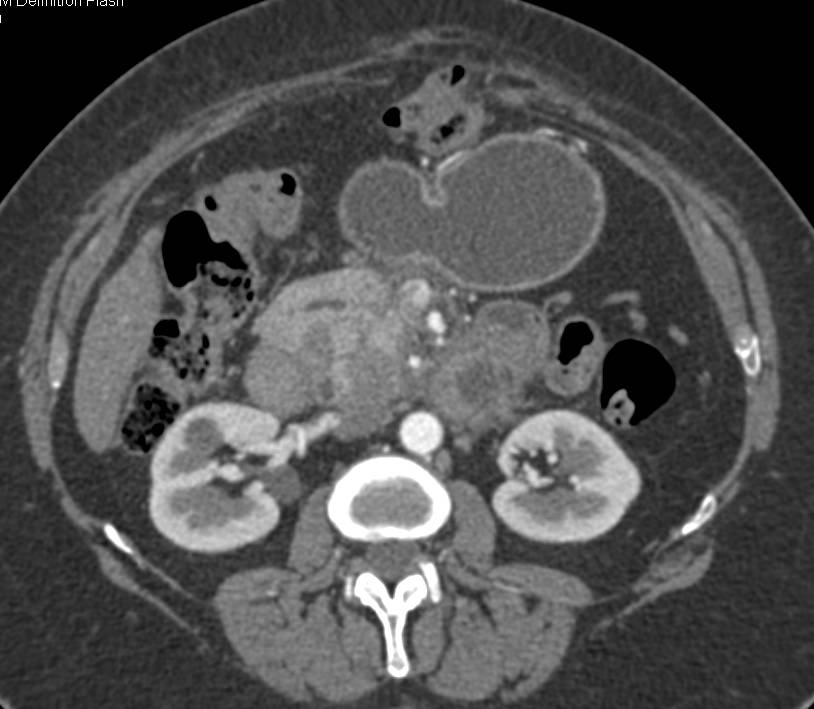

Focal Fatty Infiltration of the Pancreas Simulates a Mass